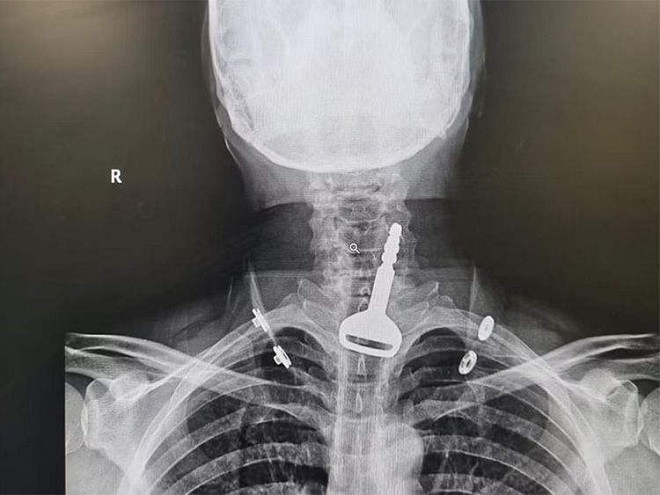

Lúc này, bệnh nhân có biểu hiện bị khó thở. Sau khi kiểm tra hình ảnh chụp X-quang, các bác sĩ phát hiện một chiếc chìa khóa ô tô nằm bên trong đường hô hấp của bệnh nhân. Người này giải thích với các bác sĩ rằng, ông ta đã vô tình nuốt phải khi đang chơi với chìa khóa xe ô tô của mình.

Tuy nhiên cho tới nay, vẫn chưa rõ bằng cách nào mà người đàn ông lại có thể nuốt được chiếc chìa khóa để suýt chết nghẹn.

Bác sĩ quyết định cách tốt nhất để lấy chìa khóa ra, và làm thông đường thở là dùng phương pháp phẫu thuật nội soi. Tuy nhiên, do nam bệnh nhân có tiền sử bệnh tim, nên quy trình phẫu thuật trở nên phức tạp hơn rất nhiều.

May mắn ca mổ nội soi đã diễn ra thành công, và bệnh nhân cũng lấy lại được chìa khóa xe ô tô. Bệnh nhân sau đó phải nằm viện vài ngày để theo dõi các biến chứng.